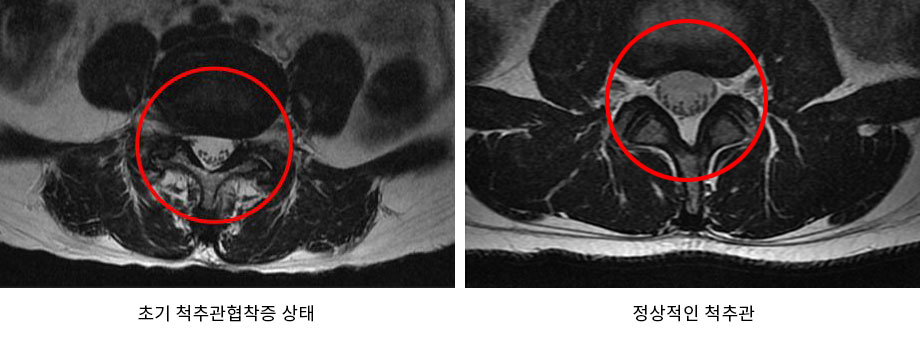

우리 몸의 중심을 잡고 체중의 대부분을 지탱해주는 척추는 나이가 들수록 퇴행되어 기능이 약해지게 됩니다. 이에 대표적인 척추질환이 퇴행성 척추관협착증입니다. 척추관협착증은 척추를 둘러싸고 있는 근육과 인대가 퇴행 되어 제 기능을 하지 못하게 되면서 척추관 내 인대가 비정상적으로 부풀어 올라 척추관의 공간이 줄어들게 되어 통증이 발생하는 질환입니다. 이러한 퇴행성 척추관협착증은 50, 60대 이상에서 발병률이 높은 질환으로 이를 방치할 경우 통증이 극심하여 거의 걷지 못하게 될 수도 있으므로 의심되는 증상이 나타난다면 초기에 치료시기를 놓치지 않는 것이 좋습니다.

초기라고 하면 대부분의 사람들은 그다지 심각하게 받아들이지 않는 경향이 있습니다. 하지만 척추협착증은 초기라도 할지라도 허리디스크보다 퇴행이 심한 상태이므로 서둘러 치료를 받는 것이 좋습니다. 척추협착증 초기증상은 일반적으로 많이 알고 있는 협착증 증상인 걸을 때 다리가 저리는 증상과는 조금 차이가 있습니다. 그렇기 때문에 환자 본인이 협착증 초기 상태임을 인지하지 못하는 경우가 많습니다. 척추협착증 초기에는 오후가 되면 다리가 뻐근하고 나무토막처럼 굳어지는 증상이 나타나거나 아침에 일어났을 때 근육이 뻣뻣해지는 조조강직감이 발생합니다. 따라서 이러한 증상들이 있다면 척추협착증 초기증상을 의심해보는 것이 좋습니다.

일반적으로 척추관협착증 초기에 치료를 시작한다면, 특히 퇴행이 극심하지 않은 초기에 치료를 시작할 경우 아침에 일어났을 때 뻣뻣했던 증상이나 오후가 되면 뻐근했던 다리 통증은 거의 없는 단계까지 회복이 될 가능성이 있습니다. 그러나 초기 협착증일 때 적절한 치료를 시작하지 않고 방치하게 되면 시간이 지날수록 중증 척추관협착증으로 진행될 가능성이 높아집니다. 중증 척추관협착증으로 진행이 되면 실제 걸을 때 통증이 발생하며 걷는 거리가 점점 짧아지게 됩니다. 또한 중증 척추관협착증은 치료 자체는 잘 된다고 하더라도 치료의 결과는 초기와 비교했을 때 다소 떨어질 수밖에 없습니다. 즉, 척추관협착증은 척추의 퇴행 정도와 증상의 정도에 따라 치료의 결과가 달라지므로 초기일 때 치료를 서둘러 시작하는 것이 매우 중요합니다. 간혹, 증상은 심하지 않으나 퇴행이 극심한 경우가 있습니다. 이런 경우 한번 증상이 발생하게 되면 급속도로 악화될 수 있기 때문에 MRI 검사와 임상증상을 꼼꼼하게 비교해봐야 합니다. 이는 증상만 초기라고 말할 수 있을 뿐 실제 척추관협착증 초기라고 보기는 어렵습니다. 이런 경우 증상이 심하지 않을 때 치료를 시작하면 증상이 악화된 후 치료를 시작했을 때보다 치료효과가 좋습니다.